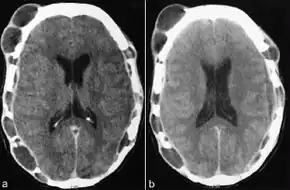

CT scan showing multiple lytic lesions of the skull[14]

Tests usually include imaging using MRI.[5] Findings include breakdown of bone and thickening of the pituitary stalk. The perivascular space may appear prominent, the pituitary gland cystic and there may be signs in the white matter, a mass in the hypothalamus and enhancement of the meninges.[5]